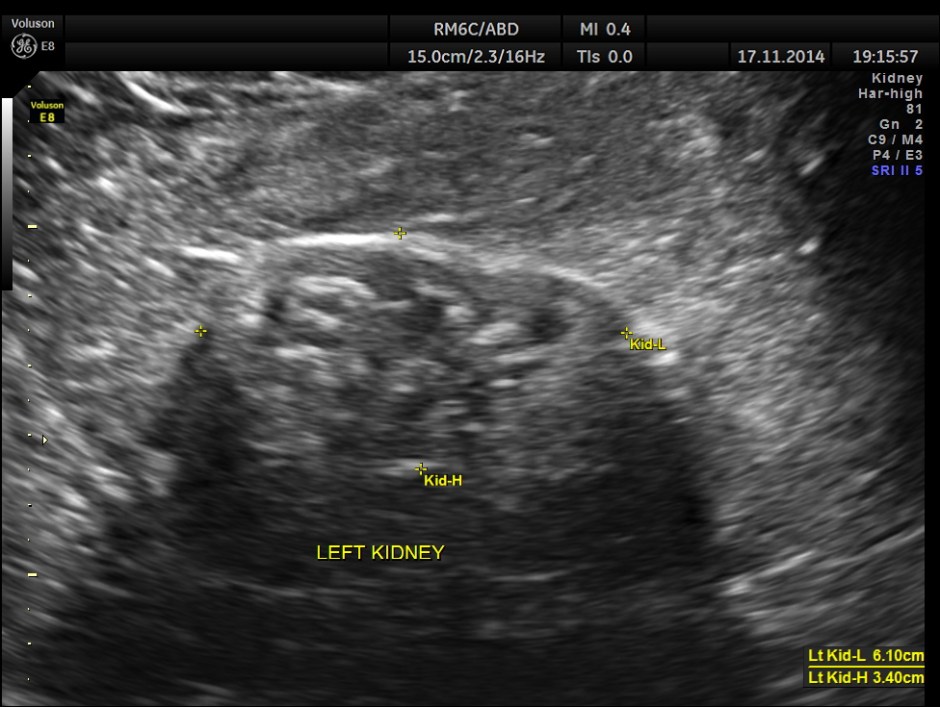

The following pictures show the native kidneys – shrunk with loss of renal architecture , with poor flow seen in Power Doppler.